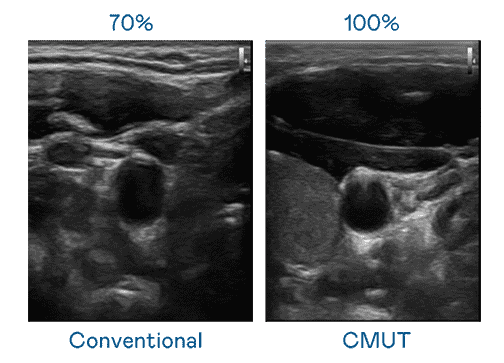

CMUT 技术是一种用电容式微机电元件来产生超音波讯号的技术。。。与传统 PZT 压电式技术相比,,CMUT 频宽增加 30%,,,更宽频的超音波讯号让影像解析度大幅提升,,是实现高影像品质医疗超音波扫描、、、、促进精准医疗发展的关键技术。。。。

大频宽带来超清晰影像

超音波影像的解析度高低,,首先取决于探头能发出的讯号频宽。。。口袋牛店 CMUT 可提供高清晰的超音波讯号,,,提供高频宽、、、、高灵敏度、、影像纹理细节更高的超音波影像,,协助医护人员缩短影像判读时间及利用精准的医疗影像进行诊断。。。。